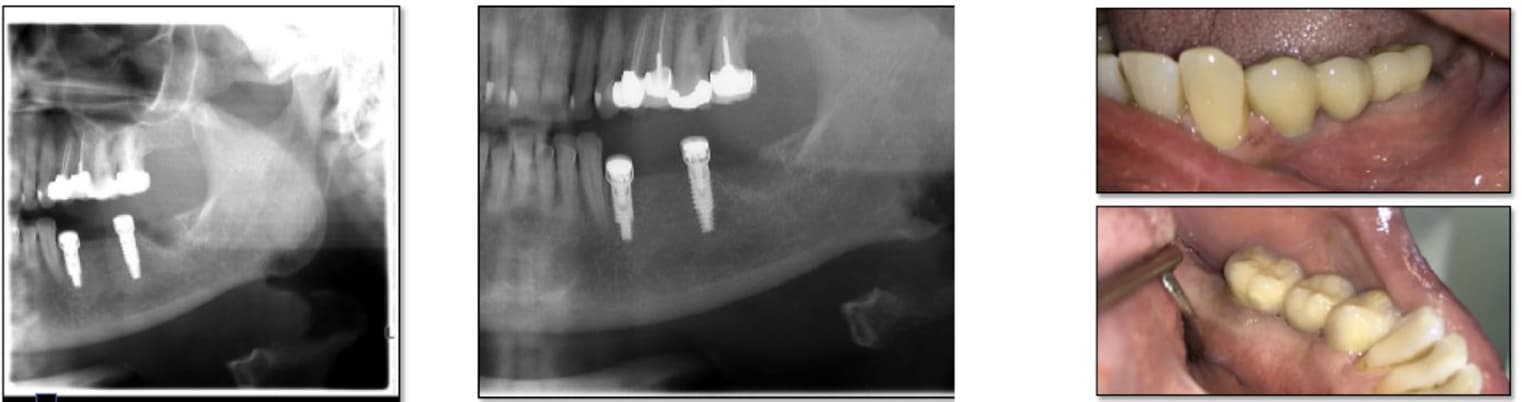

A healthy patient underwent implant placement utilizing two MED healing abutments positioned on two adjacent implants. The treatment progressed uneventfully, showing excellent soft tissue response and rapid healing. After approximately two months, radiographic evaluation confirmed successful osseointegration, enabling impression taking and preparation for the final prosthesis.

Within 81 days from the initial placement, the patient received a fixed dental bridge supported by the two adjacent implants. The case demonstrated stable osseointegration, healthy peri-implant soft tissue, and optimal esthetic results. The use of MED healing abutments facilitated enhanced bone regeneration and contributed to a predictable, efficient restorative workflow.